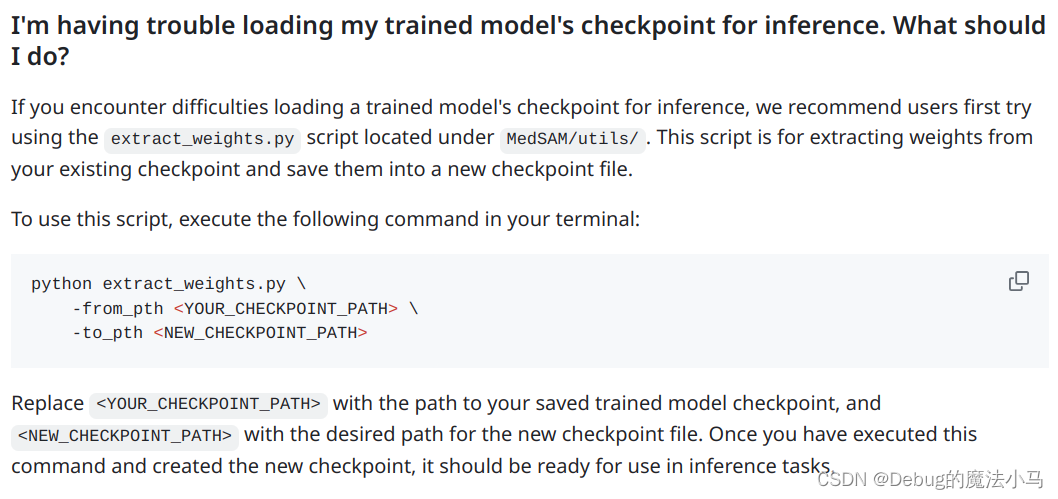

又回来了!一直觉得把load_state的参数改成false是不对的,今天果然发现问题了。因为昨天要录运行docker的演示视频,把这个项目网站又打开了。今天想再看一遍readme,结果就发现了上次漏掉的地方:

嗨呀!原来他有个提取参数的脚本啊。于是我在utils文件夹下新建脚本extract_weights.sh,赋予执行权限,并写入:

#!/bin/bash

~/anaconda3/envs/MEDSAM/bin/python extract_weights.py \

-from_pth /home/lcy-magic/MedSAM/MedSAM/work_dir/medsam_lite_latest.pth \

-to_pth /home/lcy-magic/MedSAM/MedSAM/work_dir/extracted__latest.pth

然后执行,就获得了extracted__latest.pth。

然后更改inference_3D.sh中模型参数地址为:

-medsam_lite_checkpoint_path work_dir/extracted__latest.pth \

然后再把inference_3D.py中加载参数的要求改为strict:

medsam_lite_model.load_state_dict(medsam_lite_checkpoint, strict=True)

然后运行inference_3D.sh,成功: